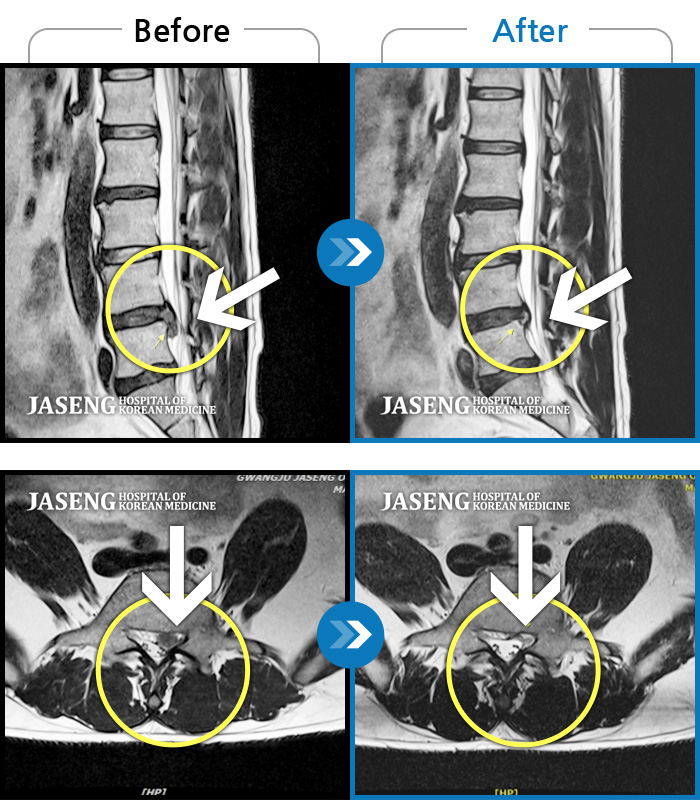

입원하기 전 후의 허리상태는 극과 극으로 너무 좋아져서 행복합니다.